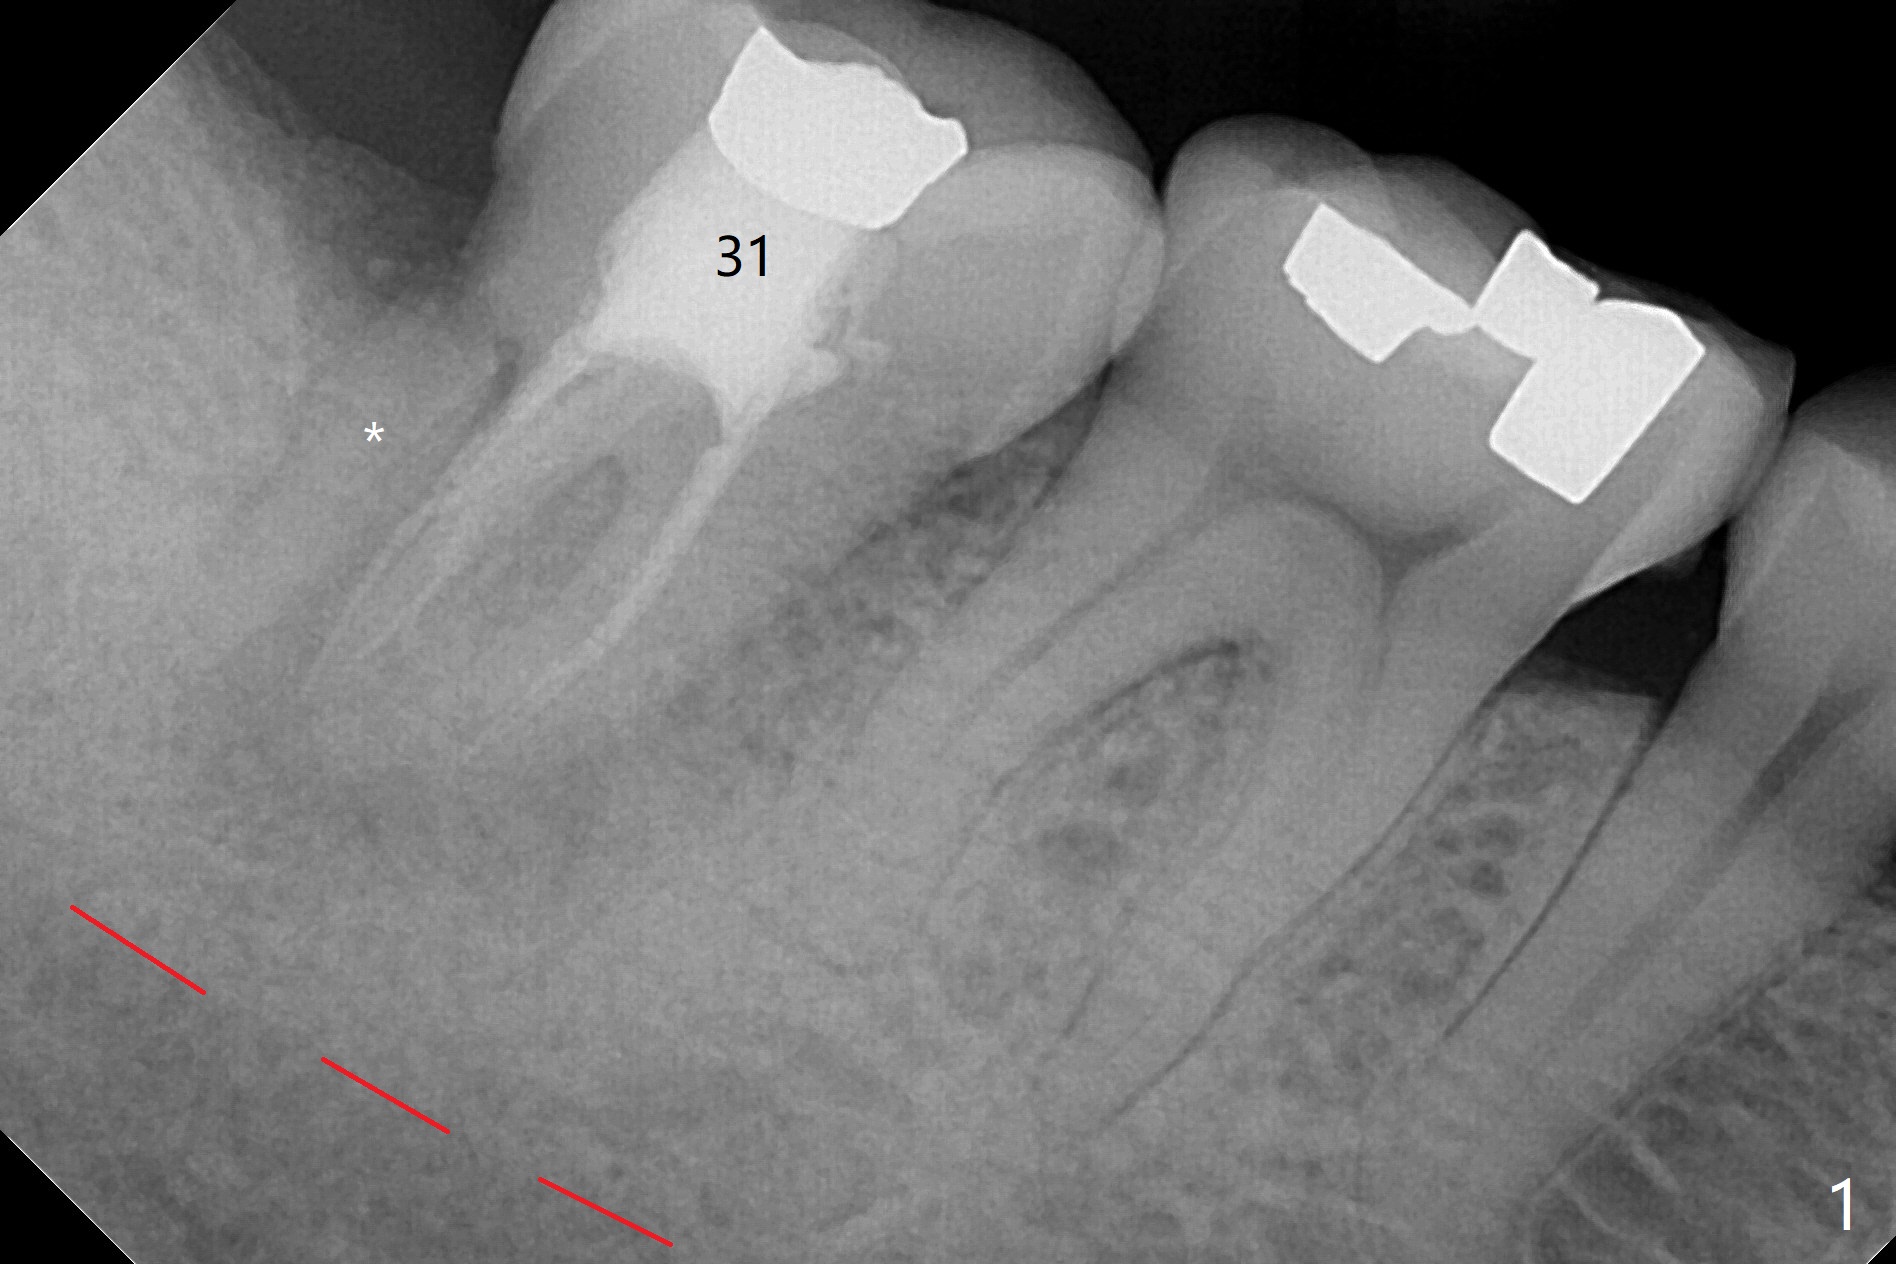

After immediate implant at #3, the tooth #31 with distal root fracture (Fig.1 *) and being close to the Inferior Alveolar Canal (red dashed line) is extracted for socket preservation (Fig.2 yellow dashed line). Although no PRF membrane is used to cover the socket, allograft is mixed with PRF liquid. A piece of 6-month membrane is used instead. The bone density is average 1000 units (Fig.3) and the ridge height is maintained 6 months postop (Fig.4). In fact the bone density of the grafted bone is low as compared to that of the native one.